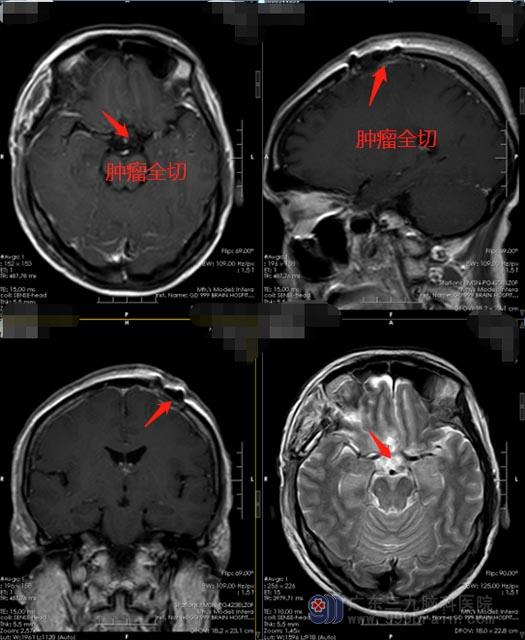

医院副院长、神经外五科主任鲁明考虑到,周阿姨颅内有不同部位的两个肿瘤,并且挤压视神经及右侧大脑前动脉,和血管关系也很密切;手术切除是最有效的治疗方法,因肿瘤与视路、垂体、下丘脑、海绵窦、颈内动脉及其分支关系紧密,手术全切除难度较大。家属了解手术风险后,经过充分考虑,同意手术治疗。鲁明带领手术团队从右侧翼点入路行右侧额底鞍旁脑膜瘤切除,再定位左侧额部,将左侧额部的脑膜瘤一并完整切除。手术非常成功,杨阿姨术后恢复很好,未出现术后并发症。